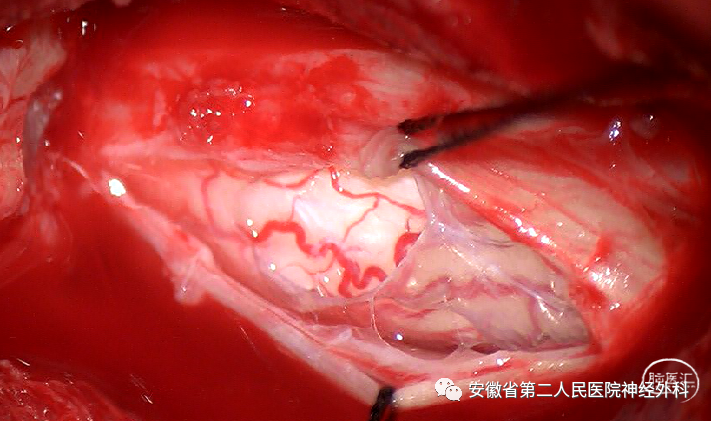

后正中半椎板入路切除神经根处肿瘤,探查松解神经根出椎间孔处

术后病理:神经鞘瘤